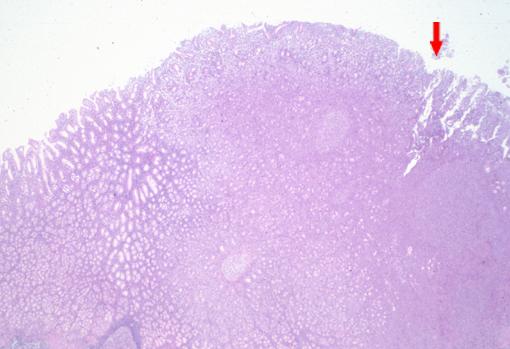

呈类似溃疡局限型胃癌形态的进行性胃恶性淋巴瘤的病理组织照片(微观)   这是一张低倍率的病理组织照片,表示与正常部分的界限。从箭头开始,左侧为正常粘膜,箭头起右侧,为病变部分。在病变部分可看到粘膜上有糜烂形成。

疾病(病理主体)的分类恶性淋巴系肿瘤/恶性淋巴瘤

检查方法病理切片(微观)

肿瘤的肉眼分类2型(溃疡局限型)/

肿瘤最大直径40以上

肿瘤的深度ss(a1)